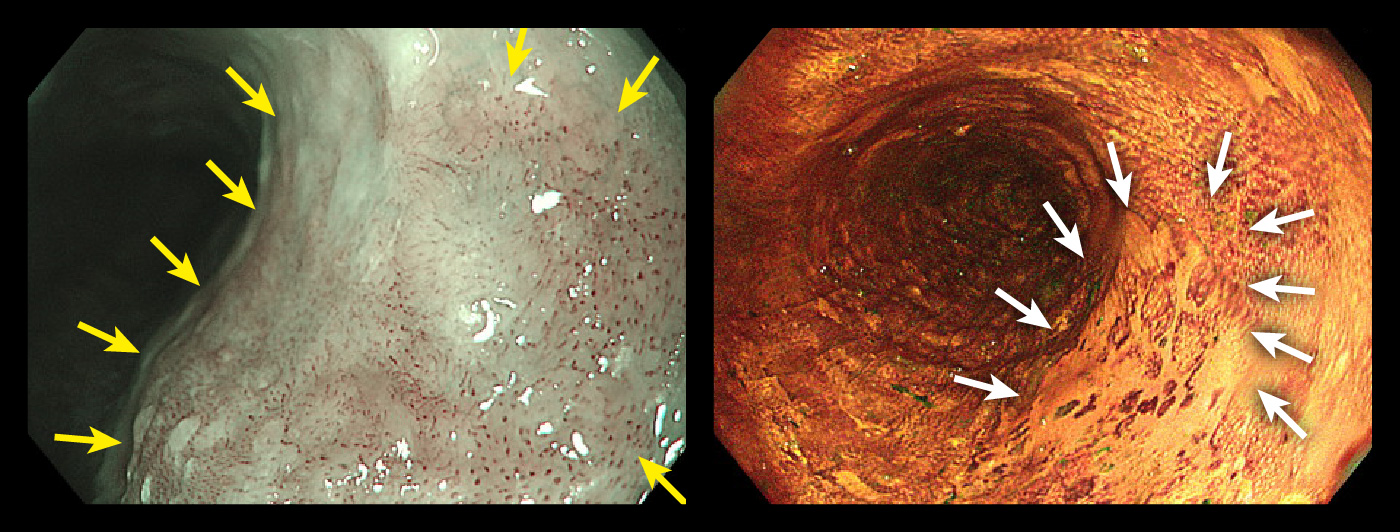

症例②

早期食道がん

左:NBI 軽度拡大/右:ルゴール散布

症例③

左:NBI 軽度拡大/右:TXI-mode2